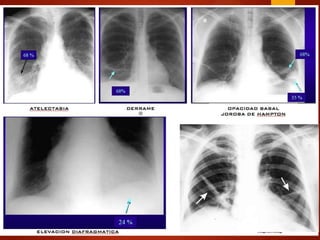

Radiología  Oligohemia  Aumento de la arteria pulmonar  Pérdida de volumen  Atelectasia  Derrame pleural  Embolismo pulmonar con infarto